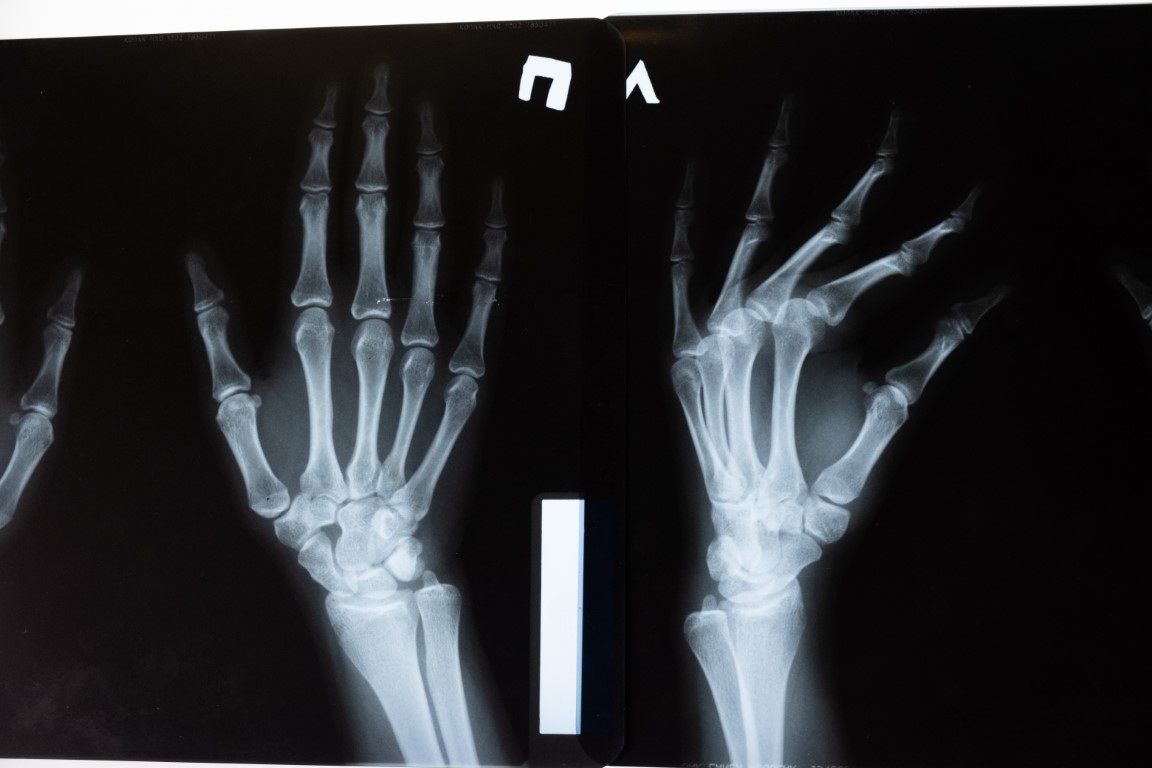

Na przełomie XIX i XX wieku głównym środkiem przekazu informacji była prasa. O ile doniesienia naukowe rozchodziły się pośród naukowców zamkniętymi ścieżkami w formie listów, wykładów i opracowań, a odbiorcami były osoby zajmujące się tą tematyką lub mające podstawy pozwalające zrozumienie tych zjawisk, tak społeczeństwo podatne było na wszelkiego rodzaju „nowinki” związane z czymś, czego nie można zobaczyć. Zobaczyć jednak można skutki, jakie powoduje działanie promieniowania jonizującego na wspomnianych wcześniej kliszach fotograficznych. Organizowano zatem pokazy uliczne, gdzie wykorzystywano urządzenia wytwarzające promieniowanie X i prześwietlano wybraną spośród widzów osobę. Możemy sobie wyobrazić jak bardzo szokujące mogło być oglądanie na takim zdjęciu kości dłoni, nogi czy też klatki piersiowej żywej osoby. Z pewnością wywoływało to zdziwienie i fascynację, a ponieważ takie jednorazowe prześwietlenie nie powodowało żadnych widocznych skutków, również i brak obaw.